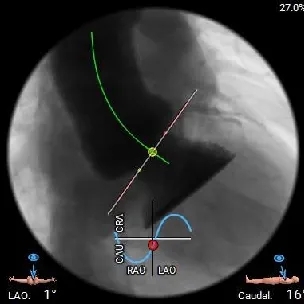

左右重叠体位:RAO 22° CAU 40° ,左冠切线位:LAO 23° CRA 17°;

工作体位

左右重合